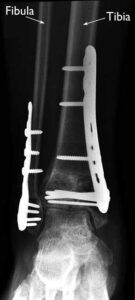

(Left) A pilon fracture often affects both bones of the lower leg. (Right) In this x-ray, both the tibia and fibula are fractured and the pieces of bone are severely displaced.